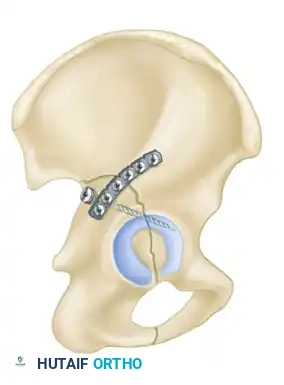

1. Percutaneous Fixation: Limited column fixation using percutaneous fluoroscopic techniques to prevent gross displacement, allowing the fracture to heal in a stable position prior to a delayed Total Hip Arthroplasty (THA).

2. Acute Total Hip Arthroplasty: Primary THA combined with limited internal fixation (to stabilize the acetabular shell) is increasingly advocated for elderly patients with poor prognostic fracture patterns, allowing immediate full weight-bearing.